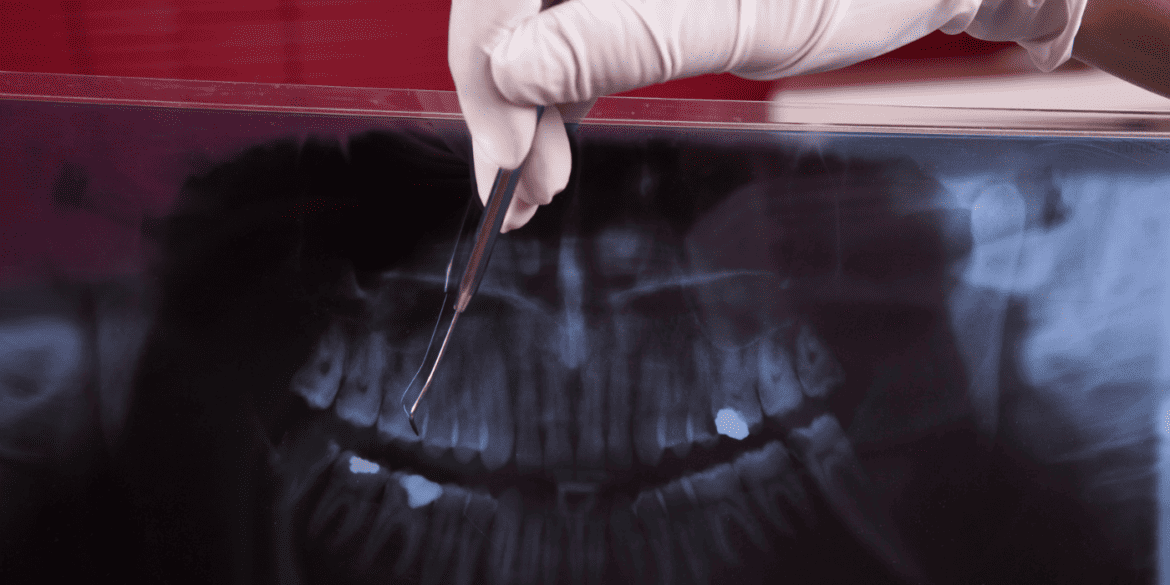

Between 1989 and 1992, seven young backpackers went missing while hitchhiking between Sydney and Melbourne. Most were taken in pairs, one alone. Their bodies were found partially buried within five kilometres in Belanglo State Forest. Forensic expert Professor Chris Griffiths has helped solve some of Australia’s most high-profile crimes using forensic dentistry. In this episode of Crime Insiders: Forensics, Griffiths explains how he helped police identify one of the victims using dental records and a mouthguard: Once the murders reached … Continue reading How Forensic Dentistry Helped Catch Ivan Milat